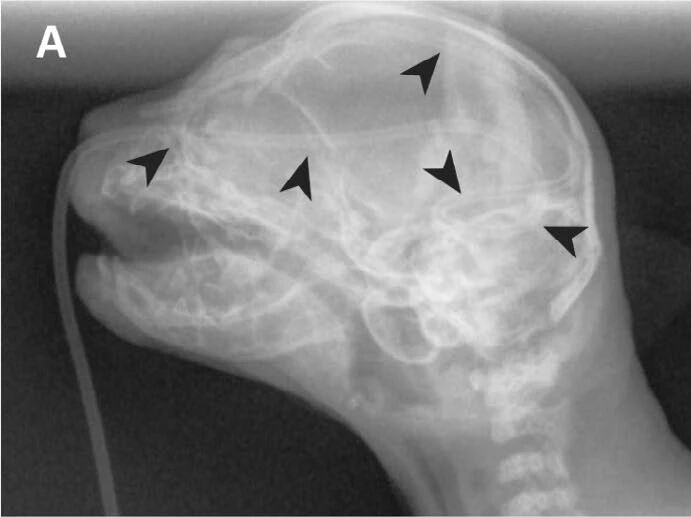

在初次就诊5天后,因疑似呼吸衰竭而心脏骤停,依照主人要求未进行心肺复苏。对大脑进行的死后MRI显示的结果符合脑部异物创伤性插入和移除,包括贯穿右脑半球的出血通道,交叉到左脑半球和小脑幕(下图B–E)。

↑ 在耳鼓泡和小脑幕的水平上获取的T2加权中线矢状图像(B)以及T1加权(C)和T2加权(DE)横断面图像显示出出血路径延伸至右脑半球(C; 星号),穿越中线涉及左脑半球(BD; 箭头)和小脑幕及后颅窝(E; 箭头)。